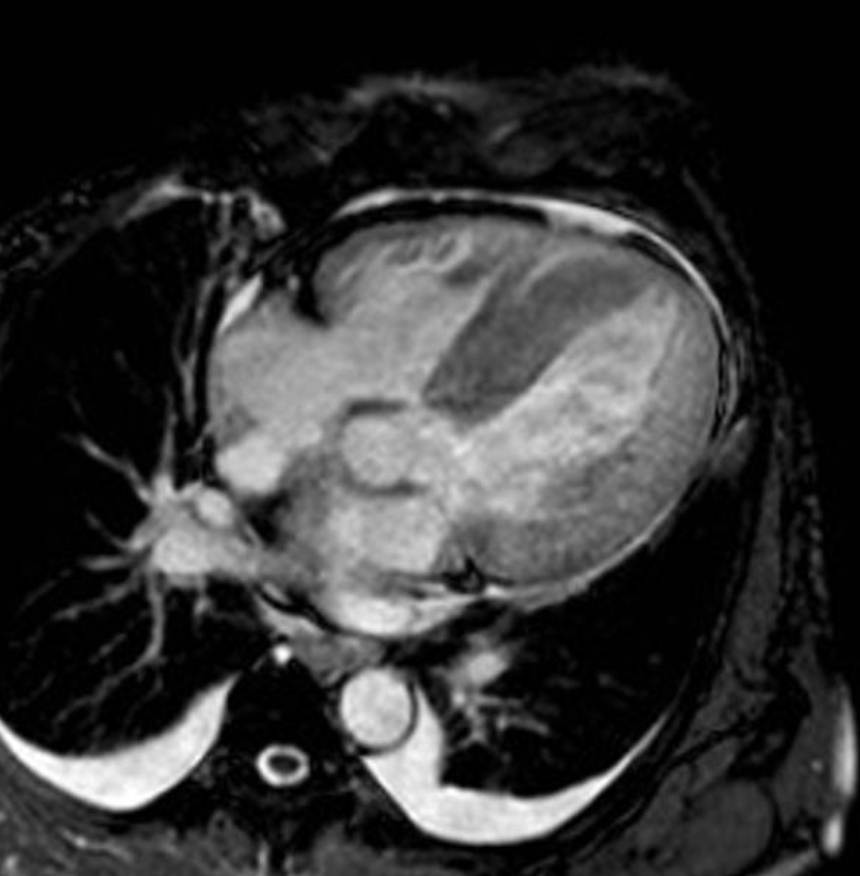

6) 심장 자기공명영상

출처 : https://radiopaedia.org/articles/restrictive-cardiomyopathy?lang=us

Restrictive cardiomyopathy | Radiology Reference Article | Radiopaedia.org

Restrictive cardiomyopathy is the least common subtype of cardiomyopathy and is characterized by a marked decrease in ventricular compliance. Clinical presentation Patients can present with symptoms and signs of left ventricular failure and/or...

radiopaedia.org

- 심장자기공명영상 : 민감도가 높은 검사법